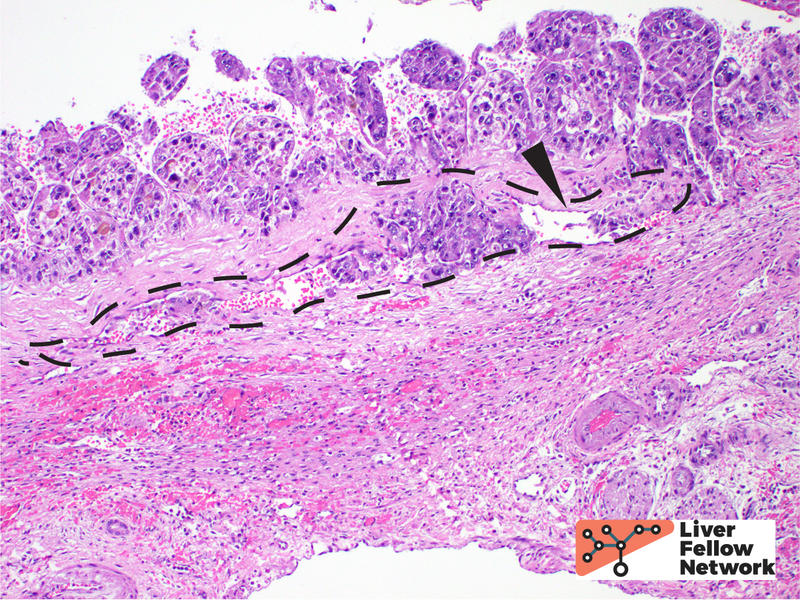

HCC is often treated by ablation or radioablation prior to surgical resection (Figure 9). In such cases, the role of the pathologist is not only to confirm the diagnosis, but to report on response to therapy and provide additional prognostic information (such as presence of lymphovascular invasion, Figure 10).